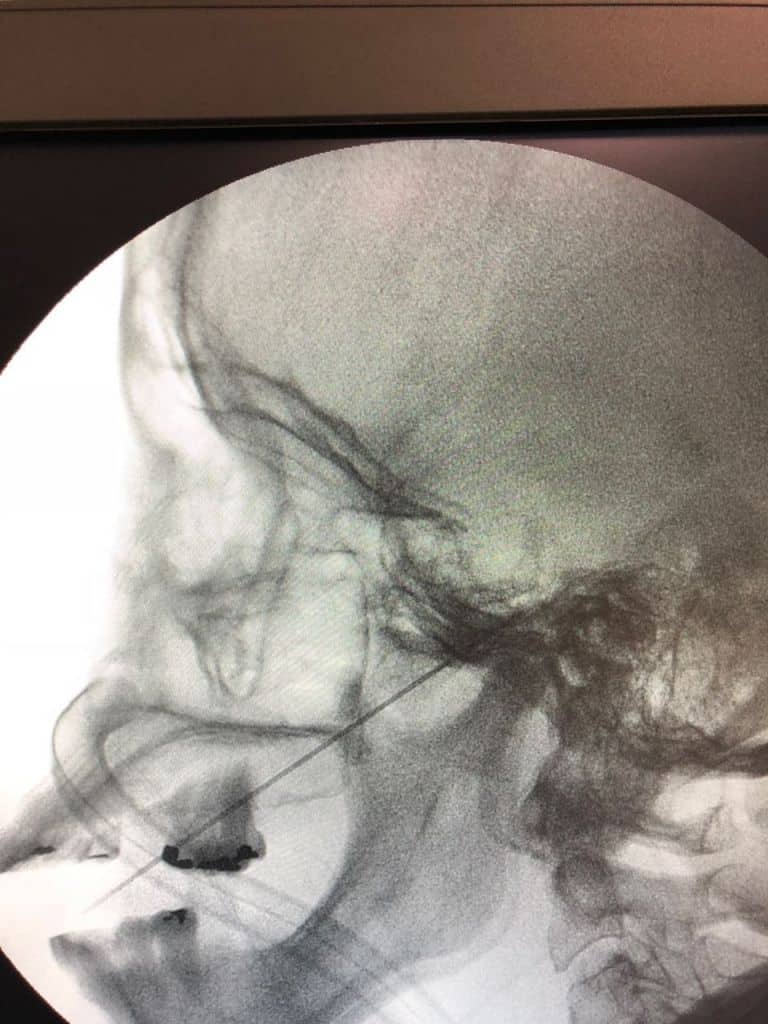

Existem várias possibilidades de tratamento cirúrgico, a depender da origem da Neuralgia e risco cirúrgico do paciente. A cirurgia com maior taxa de melhora e resultados mais duradouros é a descompressão microvascular. Porém, em alguns pacientes é necessária a realização de tratamento menos invasivos, como a rizotomia.

A rizotomia, como demonstrada na imagem, é realizada através de uma punção com agulha na face guiada por raio X. Em seguida é realizada lesão do nervo trigêmeo através de calor, compressão ou química. É um procedimento seguro e com uma taxa de melhora imediata da dor em torno de 90%.